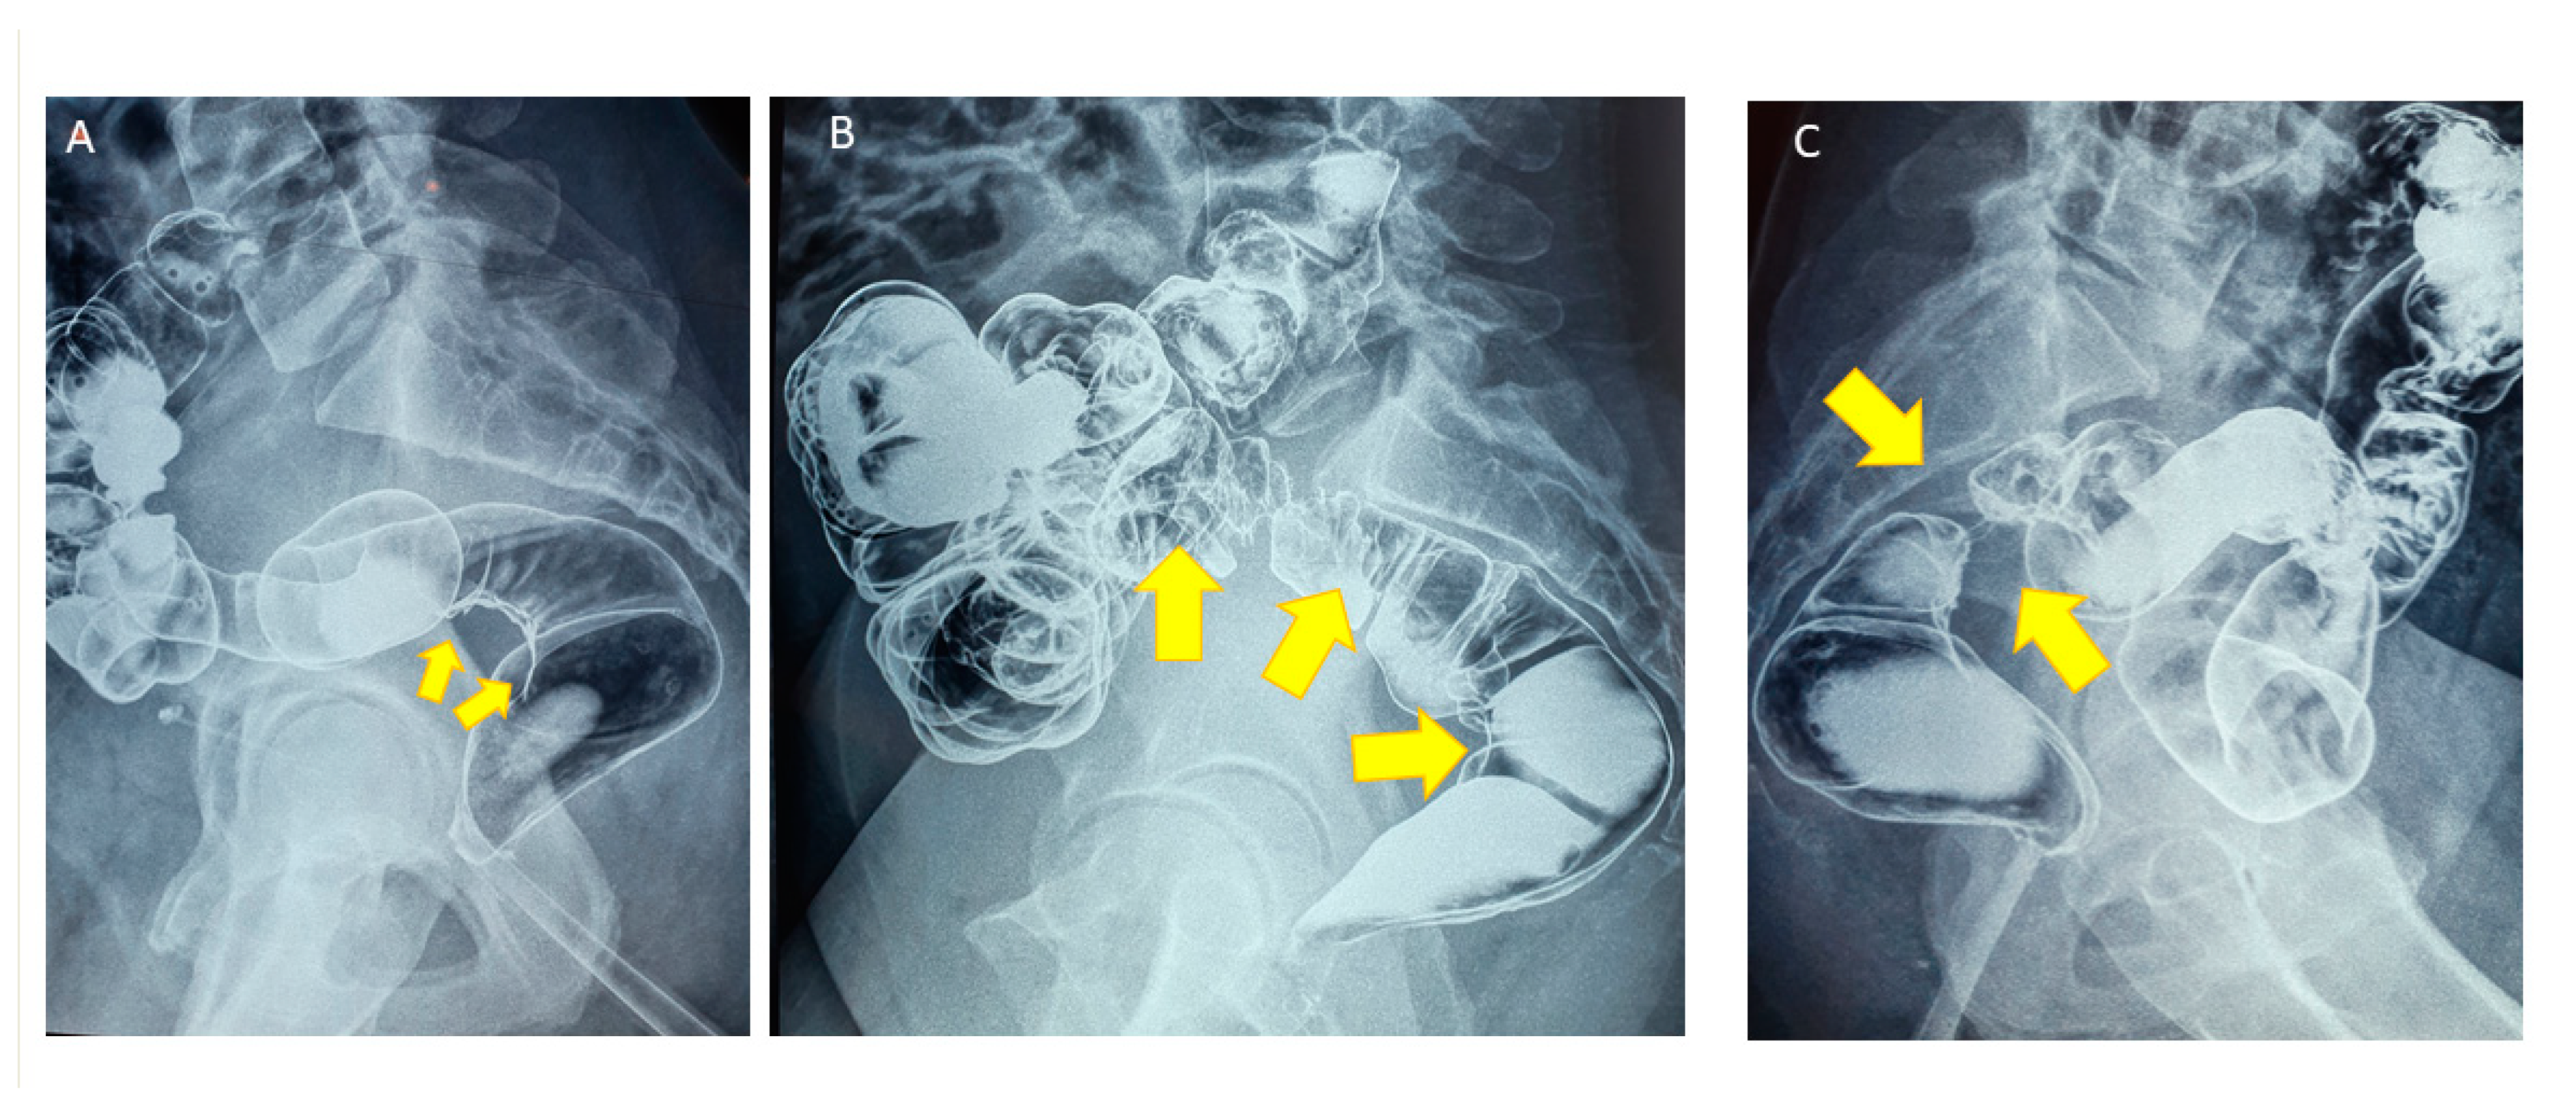

- Biscaldi, E.; Barra, F.; Leone Roberti Maggiore, U.; Ferrero, S. Other imaging techniques: Double-contrast barium enema, endoscopic ultrasonography, multidetector CT enema, and computed tomography colonoscopy. Best Pract. Res. Clin. Obstet. Gynaecol. 2021, 71, 64–77. [Google Scholar] [CrossRef] [PubMed]

- Anaf, V.; El Nakadi, I.; De Moor, V.; Coppens, E.; Zaeleman, M.; Noel, J.C. Anatomic significance of a positive barium enema in deep infiltrating endometriosis of the large bowel. World J. Surg. 2009, 33, 822–827. [Google Scholar] [CrossRef]